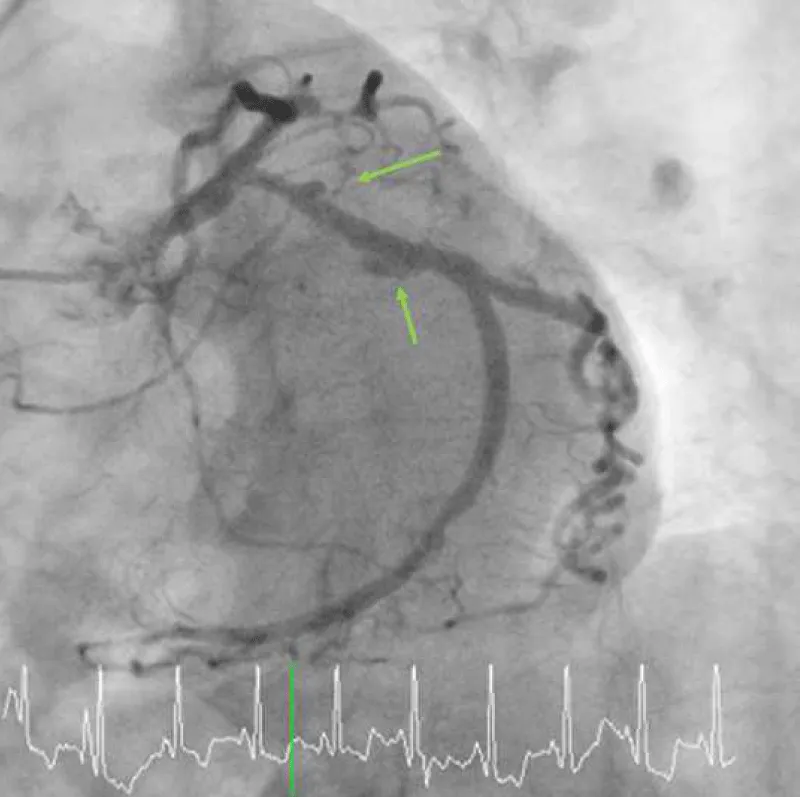

A 75-year-old woman presented with new-onset Canadian Cardiovascular Society Classification Class III angina. A coronary angiogram revealed a 90% blockage of the distal left main trunk (LMT) and a 99% blockage of the ostial left anterior descending coronary artery (LAD) (Video 1A) and (Video 1B). The Syntax Score, Society of Thoracic Surgeons (STS) score and left ventricular ejection fraction (LVEF) were 28, 1.65% and 74%, respectively. A 3.0 × 18-mm CYPHER™ stent had previously been implanted into the dominant proximal circumflex artery (LCx) in 2009 because of unstable angina (Figures 1A,1B). Although some persistent peri-stent contrast staining (PSS) was noted on an angiogram as early as June 8, 2015 (Figure 1C), a single treatment with clopidogrel for antiplatelet therapy was interrupted 7 days before an elective CABG. The patient started complaining of chest pain that corresponded with a marked ST elevation in the inferior posterior leads (Figure 2) and subsequently collapsed on August 7, 2016, in a general ward, 5 days after clopidogrel was discontinued. The patient had a history of dyslipidemia and hypertension but not diabetes, prior cerebrovascular accident, or chronic obstructive pulmonary disease. Her medication included clopidogrel (75 mg), rosuvastatin (2.5 mg), nicorandil (15 mg) and benidipine (8 mg) daily. An emergent bedside echocardiogram showed posteroinferior hypokinesia without any dissection flap in the aortic root (Video 2). Following an aggressive cardiopulmonary resuscitation (CPR) in the general ward, femorofemoral venoarterial extracorporeal membrane oxygenation (VA-ECMO) was inserted in a catheterization laboratory (Video 3). An emergent angiogram revealed a thrombotic stent occlusion of the proximal LCx (Video 4A) and (Video 4B). During angiography, the patient remained pulseless and suffered repeated bouts of ventricular fibrillation, which necessitated defibrillations. When manual aspiration thrombectomy was performed, adequate coronary flow returned instantaneously (Video 5) and (Video 6) and systolic blood pressure improved to 90 mmHg. In the end, an intra-aortic balloon pump was placed and ECMO could be tapered off the same day. The maximum creatine phosphokinase and creatine kinase-MB levels were 4398 and 269 IU/mL, respectively. The following day, the patient underwent on-pump CABG with left internal thoracic artery-LAD and saphenous vein graft-obtuse marginal anastomoses. The patient survived and recovered well without any neurological defect. As of today, LVEF is 55% and single clopidogrel therapy is ongoing. Both bypass grafts and the stent were patent (Video 7).

Figure 1A: A diagnostic angiogram and PCI in 2009 and a follow-up angiogram in 2015. A baseline angiogram using a 4-Fr Judkins diagnostic catheter via transradial access shows a focal 90% blockage (yellow arrow) at the dominant proximal LCx.

Figure 1B: A 3.0 × 18-mm CYPHER™ stent was placed without any complications such as a stent-induced dissection.